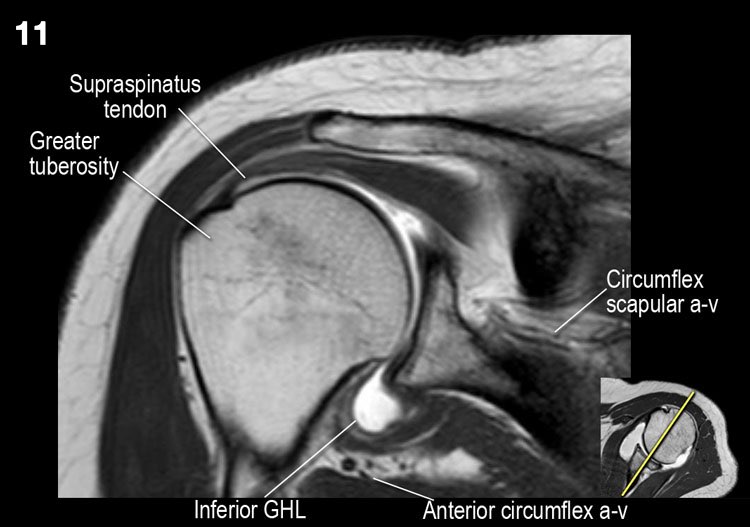

Hình ảnh mặt sau

Hình ảnh thể hiện các cơ và gân của cơ trên gai, cơ dưới gai và cơ tròn bé. Tất cả đều bám vào mấu động lớn.

Giải phẫu mặt cắt vành và danh sách kiểm tra

- Đánh giá chỗ bám của dây chằng ổ chảo-cánh tay dưới (IGHL) vào xương cánh tay. Đánh giá phức hợp sụn viền-dây chằng phần dưới. Tìm kiếm tổn thương HAGL (bong điểm bám dây chằng ổ chảo-cánh tay tại xương cánh tay).

- Lưu ý tổn thương Hill-Sachs nhỏ.

Giải phẫu mặt cắt đứng dọc và danh sách kiểm tra